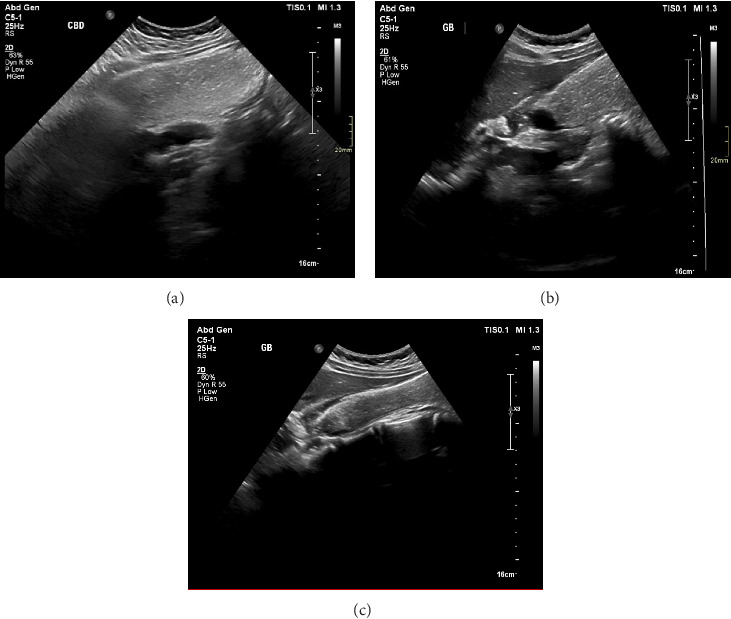

2型神经纤维瘤病(NF2),也称为NF2相关神经鞘瘤病(SWN),是一种罕见的显性遗传性遗传病,主要特征为前庭神经鞘瘤(VSs)以及一系列影响中枢和周围神经系统的其他肿瘤。这些肿瘤包括颅、脊髓、周围神经和皮内神经鞘瘤,颅和脊髓脑膜瘤,以及固有中枢神经系统(CNS)肿瘤,通常是脊髓室管膜瘤。青少年白内障在NF2患者中也很常见,大多数症状为听力丧失和视力障碍。我们提出的情况下,以前健康的12岁女孩谁提出餐后右上腹部疼痛,并被发现有一个大的胆囊积液超声扫描腹部。腹腔镜胆囊切除术后胆囊病理显示胆囊弥漫性受累于良性神经鞘肿瘤,提示神经鞘瘤。进一步的检测证实了NF2的诊断。本病例有助于阐明不寻常的NF2症状,并强调了识别非典型表现以及时干预和管理的重要性。它还增加了诊断和管理NF2的多学科方法的价值。

Neurofibromatosis type 2 (NF2), also known as NF2-related schwannomatosis (SWN), is a rare dominantly inherited genetic disorder mainly characterized by the presence of vestibular schwannomas (VSs) in addition to a range of other tumors that affect both the central and peripheral nervous systems. These tumors include cranial, spinal, peripheral nerve, and intradermal schwannomas, cranial and spinal meningiomas, and intrinsic central nervous system (CNS) tumors, usually spinal ependymomas. Juvenile cataracts are also common in patients with NF2, with most symptoms at presentation being hearing loss and visual disturbances. We present the case of a previously healthy 12-year-old girl who presented with postprandial right upper quadrant pain and was found to have a large hydrops of the gallbladder on ultrasound scan of the abdomen. Pathology of the gallbladder post laparoscopic cholecystectomy showed diffuse involvement of the gallbladder by a benign nerve sheath tumor that was suggestive of schwannoma. Further testing confirmed the diagnosis of NF2. This case helps shed light on unusual NF2 symptoms and underscores the importance of recognizing atypical presentations for timely intervention and management. It also adds value to a multidisciplinary approach in diagnosing and managing NF2.